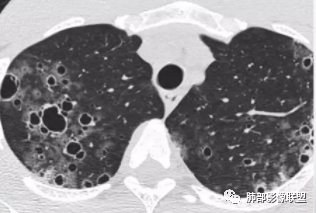

双肺多发大小不等囊腔,形态不规则,大部分囊融合,部分囊壁偏厚,部分可见磨玻璃影及多发粟粒状影,临床有交界性浆液性囊腺瘤,首先考虑囊性转移瘤,鉴别LIP,BHD。LAM,PLCH影像不符,不考虑。

双肺多发不规则囊腔,囊壁增厚,并可见散在分布的结节与实变,多层面观察较多囊腔沿支气管走行分布,年轻女性双肺多发囊,但囊腔不规则,一般不考虑Lam,有结节及囊,有实变〈粘液拴〉年轻女性,首选PLcm或ccam

直接拍死;转移,不鉴别,病理类型,多囊性间皮瘤>囊腺癌>腺癌(胸膜不规则结节性增厚伴肺内胸膜下多发结节+沿血管分布多发囊+病史大网膜间皮样增生)年轻女性有可能是腹膜多囊性间皮瘤,然后发生转移,真要是这个,难得的少见病例

晨读:女,31,间断咳嗽、咳痰9月。卵巢交界性囊腺瘤术后。胸部CT:双肺多发大小不等薄壁囊腔影,部分融合,形态不规则,个别囊壁偏厚。右肺上叶及左肺下叶纤维索条影。左下叶不规则囊腔影,壁不均匀增厚,周围不规则实性成分加GGO,放射性毛刺,胸膜牵拉。考虑:囊腔型Ca?转移?鉴别PLCH,Lam,LIp,BHD,CF,CPAM等,听大咖解析。